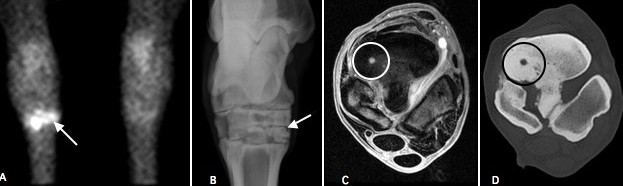

In the above image we have performed a bone scan, radiographs, MRI and CT examination. This is an uncommon example but shows how diagnostic imaging modalities can complement each other. The bone scan on the left shows a bright ‘hot spot’. A radiograph of this site does not show the reason but the MRI and CT scan show a cyst (circled). This case had a screw placed across the cyst.